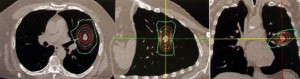

Η ακτινοχειρουργική με CyberKnife αντιπροσωπεύει μία πανίσχυρη και μεγάλης ακρίβειας τεχνική για ασθενείς με αρχική, υποτροπή ή μεταστατική εντόπιση όγκου στον πνεύμονα. Η θεραπεία είναι ασφαλής να δοθεί σε ασθενείς που δεν μπορούν λόγω άλλων παθολογικών καταστάσεων να χειρουργηθούν και προσφέρει μία πολύ καλή θεραπευτική επιλογή σε ασθενείς με υποτροπιάζουσα ή εμμένουσα νόσο που πριν είχαν ελάχιστες αν όχι καμία, δραστική θεραπεία ικανή να τους βοηθήσει.

Το CyberKnife είναι ένα σύστημα ακτινοθεραπείας που αποτελείται από ένα γραμμικό επιταχυντή τοποθετημένο επάνω σε έναν ρομποτικό βραχίονα.

Το CyberKnife είναι ένα σύστημα ακτινοθεραπείας που αποτελείται από ένα γραμμικό επιταχυντή τοποθετημένο επάνω σε έναν ρομποτικό βραχίονα.